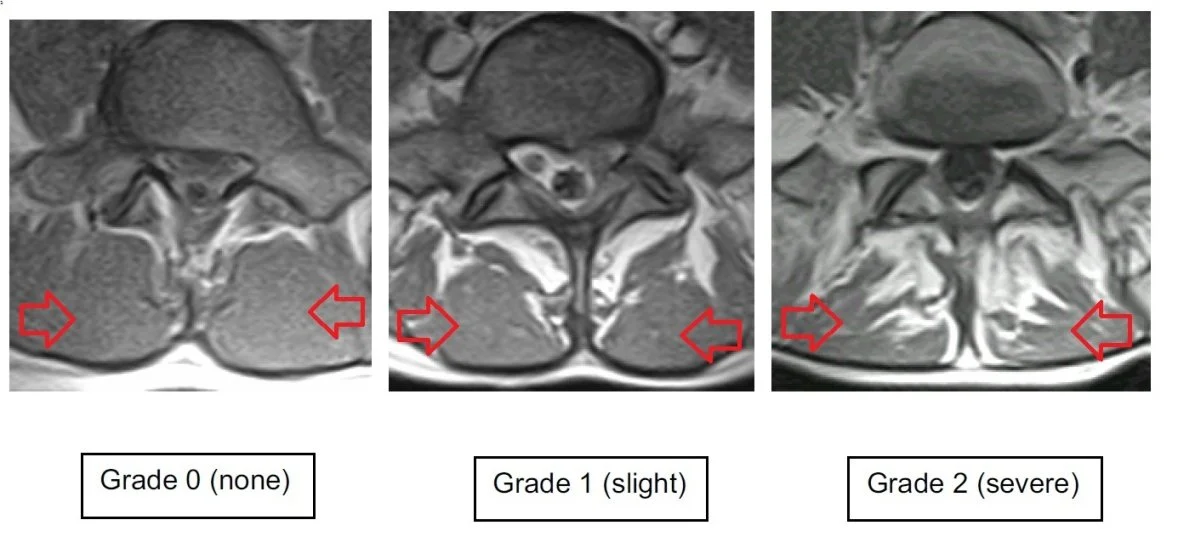

Multifidus Fatty Infiltration on MRI

In the first two blog articles we talked about the muscle Multifidus and its importance in spinal stability and decreasing low back pain. We have come across some great research1 which helps visualise the adaptive change that occurs during low back pain. The...